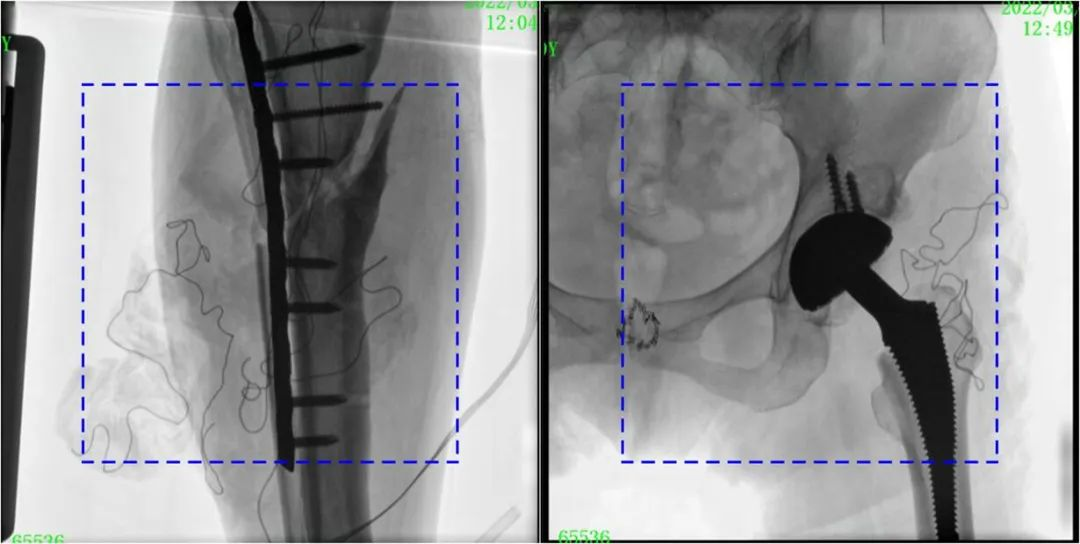

與傳統(tǒng)的21CM×21CM成像尺寸相比,普愛(ài)醫(yī)療大平板一體式C形臂具有30CM×30CM更大成像尺寸,能夠一次成像5.5節(jié)椎體,呈現(xiàn)更全面的影像信息,即便是手術(shù)經(jīng)驗(yàn)不豐富的年輕醫(yī)生也能通過(guò)圖像迅速判斷椎體節(jié)段、定位手術(shù)部位,避免因?yàn)橐曇安蛔愣斐傻亩啻味ㄎ?、反?fù)曝光,提高效率的同時(shí)避免過(guò)量攝入輻射。

普愛(ài)醫(yī)療大平板一體式C形臂圖像與傳統(tǒng)圖像對(duì)比(藍(lán)色虛線(xiàn)內(nèi)為傳統(tǒng)21CM×21CM平板的成像區(qū)域)